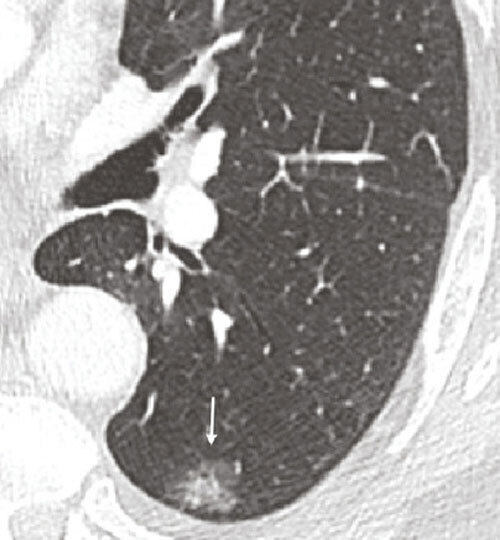

Le dépistage repose sur la réalisation d’un scanner thoracique à faible dose sans injection chez des personnes asymptomatiques ayant un risque élevé de ce cancer (fumeurs ou anciens fumeurs). En cas d'anomalie, le bilan diagnostique comporterait des examens complémentaires d'imagerie et une biopsie de la tumeur.

Une détection des cancers à un stade plus précoce a également été observée, un résultat intéressant dans le cas du cancer du poumon dont le pronostic est d'autant plus sombre qu'il est détecté à un stade tardif. La survie à 5 ans n'est ainsi que de 4 % pour une détection au stade IV, stade auquel il est aujourd'hui diagnostiqué dans 40 % à 55 % des cas.